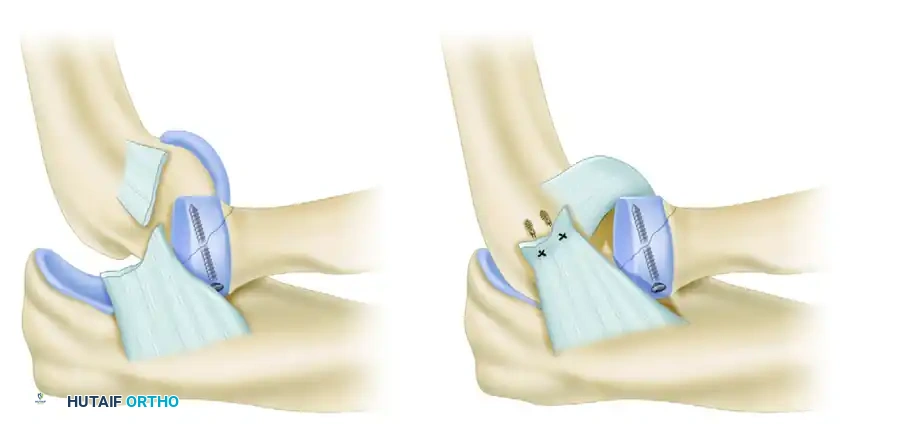

Step 4: Lateral Collateral Ligament (LCL) Repair

After coronoid and radial head stabilization, the LCL complex and the common extensor origin must be reattached to their anatomic origin on the lateral epicondyle.

The isometric point of the LCL is located at the center of capitellar curvature. Reattachment is typically performed using robust suture anchors. Krackow or locking whipstitches are placed into the avulsed ligament and tendon complex, and the anchors are deployed into the lateral epicondyle. Reestablishment of these soft tissue restraints adds greatly to the overall posterolateral rotatory stability of the elbow joint.

FIGURE 57-67 D: The avulsed lateral ligamentous complex is repaired directly to the bare spot on the lateral condyle using suture anchors.